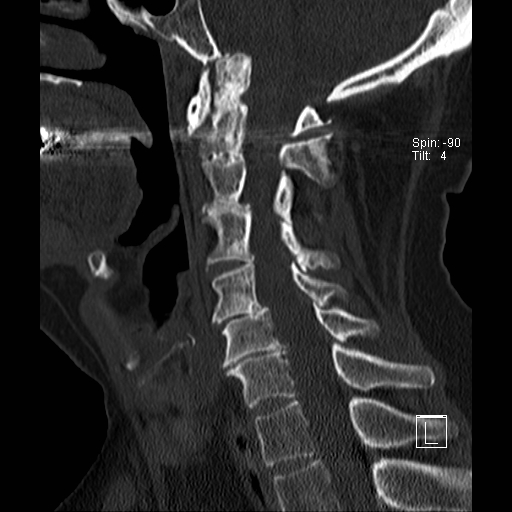

Lồng nền sọ

Lồng nền sọ, còn gọi là sụt lún sọ não hay ấn nền sọ, xảy ra ở 5-10% bệnh nhân viêm khớp dạng thấp cột sống cổ.

Trong lồng nền sọ, mỏm răng sa vào lỗ chẩm làm thu hẹp không gian dành cho tủy sống.

Biểu hiện lâm sàng đa dạng, từ đau đầu mạn tính, hạn chế vận động cổ đến suy giảm thần kinh cấp tính (chèn ép tủy sống và thân não, có thể dẫn đến liệt hoặc thậm chí tử vong nếu cổ bị di chuyển ở một số tư thế nhất định).

Hình ảnh

Cuộn xem các lát cắt CT.

Có hình ảnh di chuyển lên trên của mỏm răng vào lỗ chẩm.